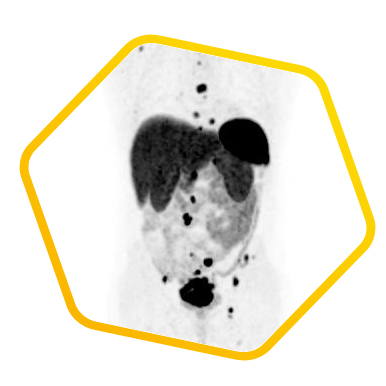

脑神经内分泌肿瘤

双示踪剂PET/CT (F-18 FDG及Ga-68 DOTATATE) 用於评估脑神经内分泌肿瘤体内的扩散情况

![]() [Ga-68] DOTATATE |